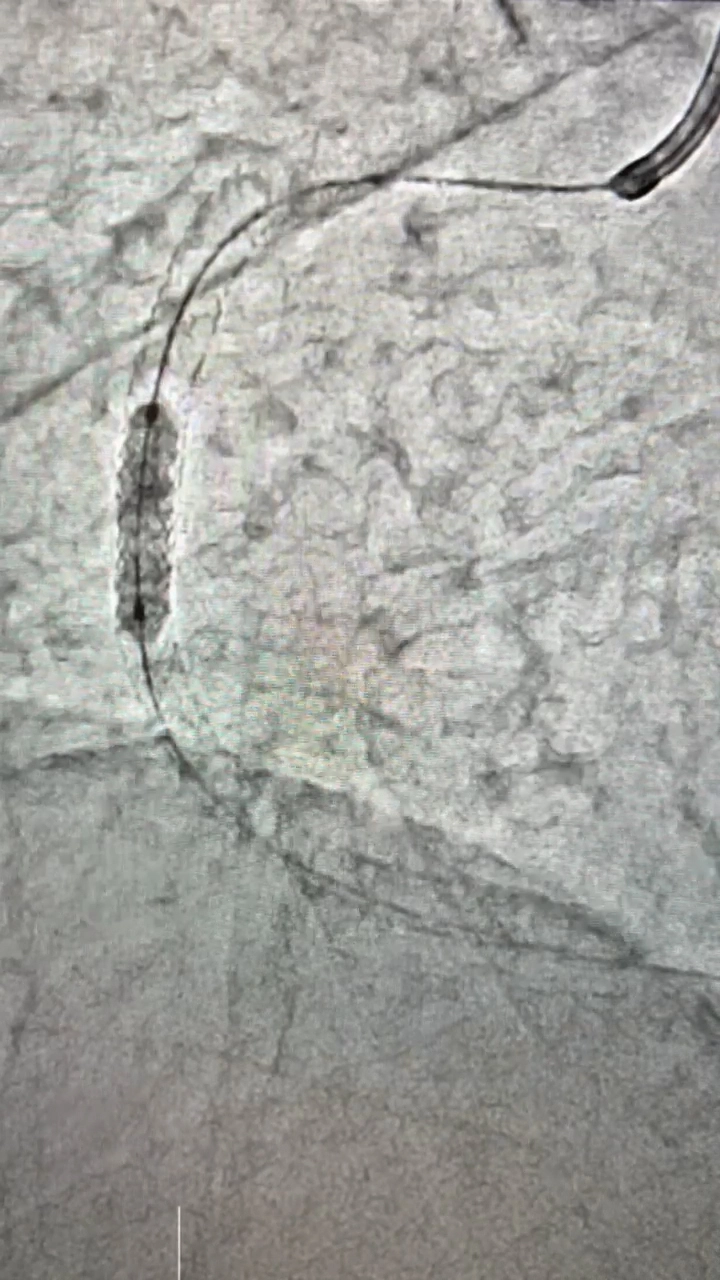

血管造影検査・治療

従来の血管撮影装置よりも、少ないX線量で鮮明な撮影を行なうことができます。心血管検査では一度に広範囲の撮影・診断が可能となり、高精度の検査・治療が行なえます。

また、脳血管検査では脳梗塞の原因となっている血栓の吸引、出血している血管の特定も行なうことができます。

カテーテル検査

検査にはカテーテルという細い管を用いて、血管内に造影剤や薬剤を直接注入することで、狭窄部位や腫瘍などの検索、または治療を行ないます。

心臓カテーテル、血管の3次元画像(3D)など多種にわたって検査することができ、原因疾患の特定にもとても有効な検査です。

検査だけではなく治療も

脳動脈瘤による出血、血栓による脳梗塞、腹部外傷による出血などもカテーテルを使い、わずかな傷で治療を行なうことが可能です。